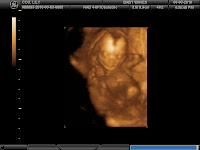

4D ultrasound pictures are in

Morgs and I visited Baby Waves this afternoon to have Ellie's picture taken. Here are the results:

Isn't she precious? Video to follow.